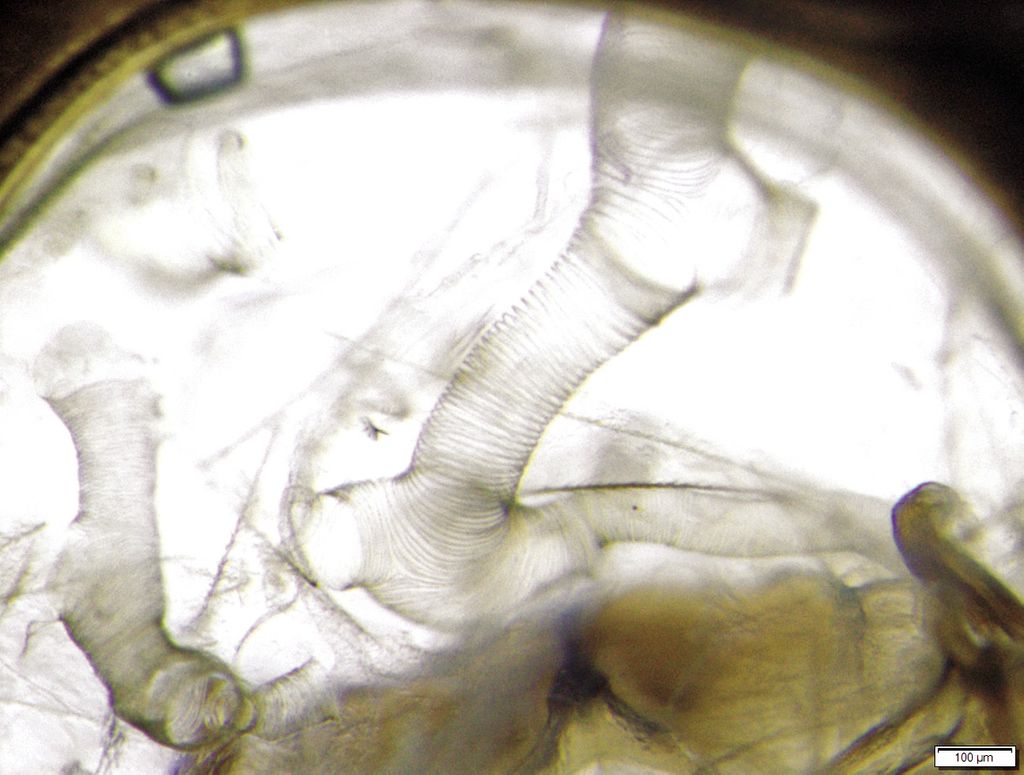

Foto 2. Prima pereche de tuburi traheale ale albinei.

Fotograf Andrzej Bober.

Acarapis woodi (foto 1) este un parazit obligatoriu care trăiește și se reproduce în prima pereche de tuburi traheale (foto 2, foto 3), a fost observat și la nivelul sacului aerian de cap, tors și abdominal. Parazitul este dioic.